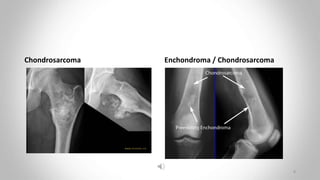

Chondrosarcoma

• mainly in the 30–50-year-old age group.

• most commonly in the pelvic bones, scapulae ,humerus and femur.

• a lytic expanding lesion containing flecks of calcium, a sign that

indicates its origin from cartilage cells.

• diffcult to distinguish from its benign counterpart, the enchondroma.

 chondrosarcoma is usually less well defined in at least one portion

of its outline

 it may show a periosteal reaction

• Pelvic chondrosarcomas often have large extraosseus soft tissue components best seen with CT

or MRI

• may arise from malignant degeneration of a benign cartilagenous tumor

Chondrosarcoma Enchondroma / Chondrosarcoma